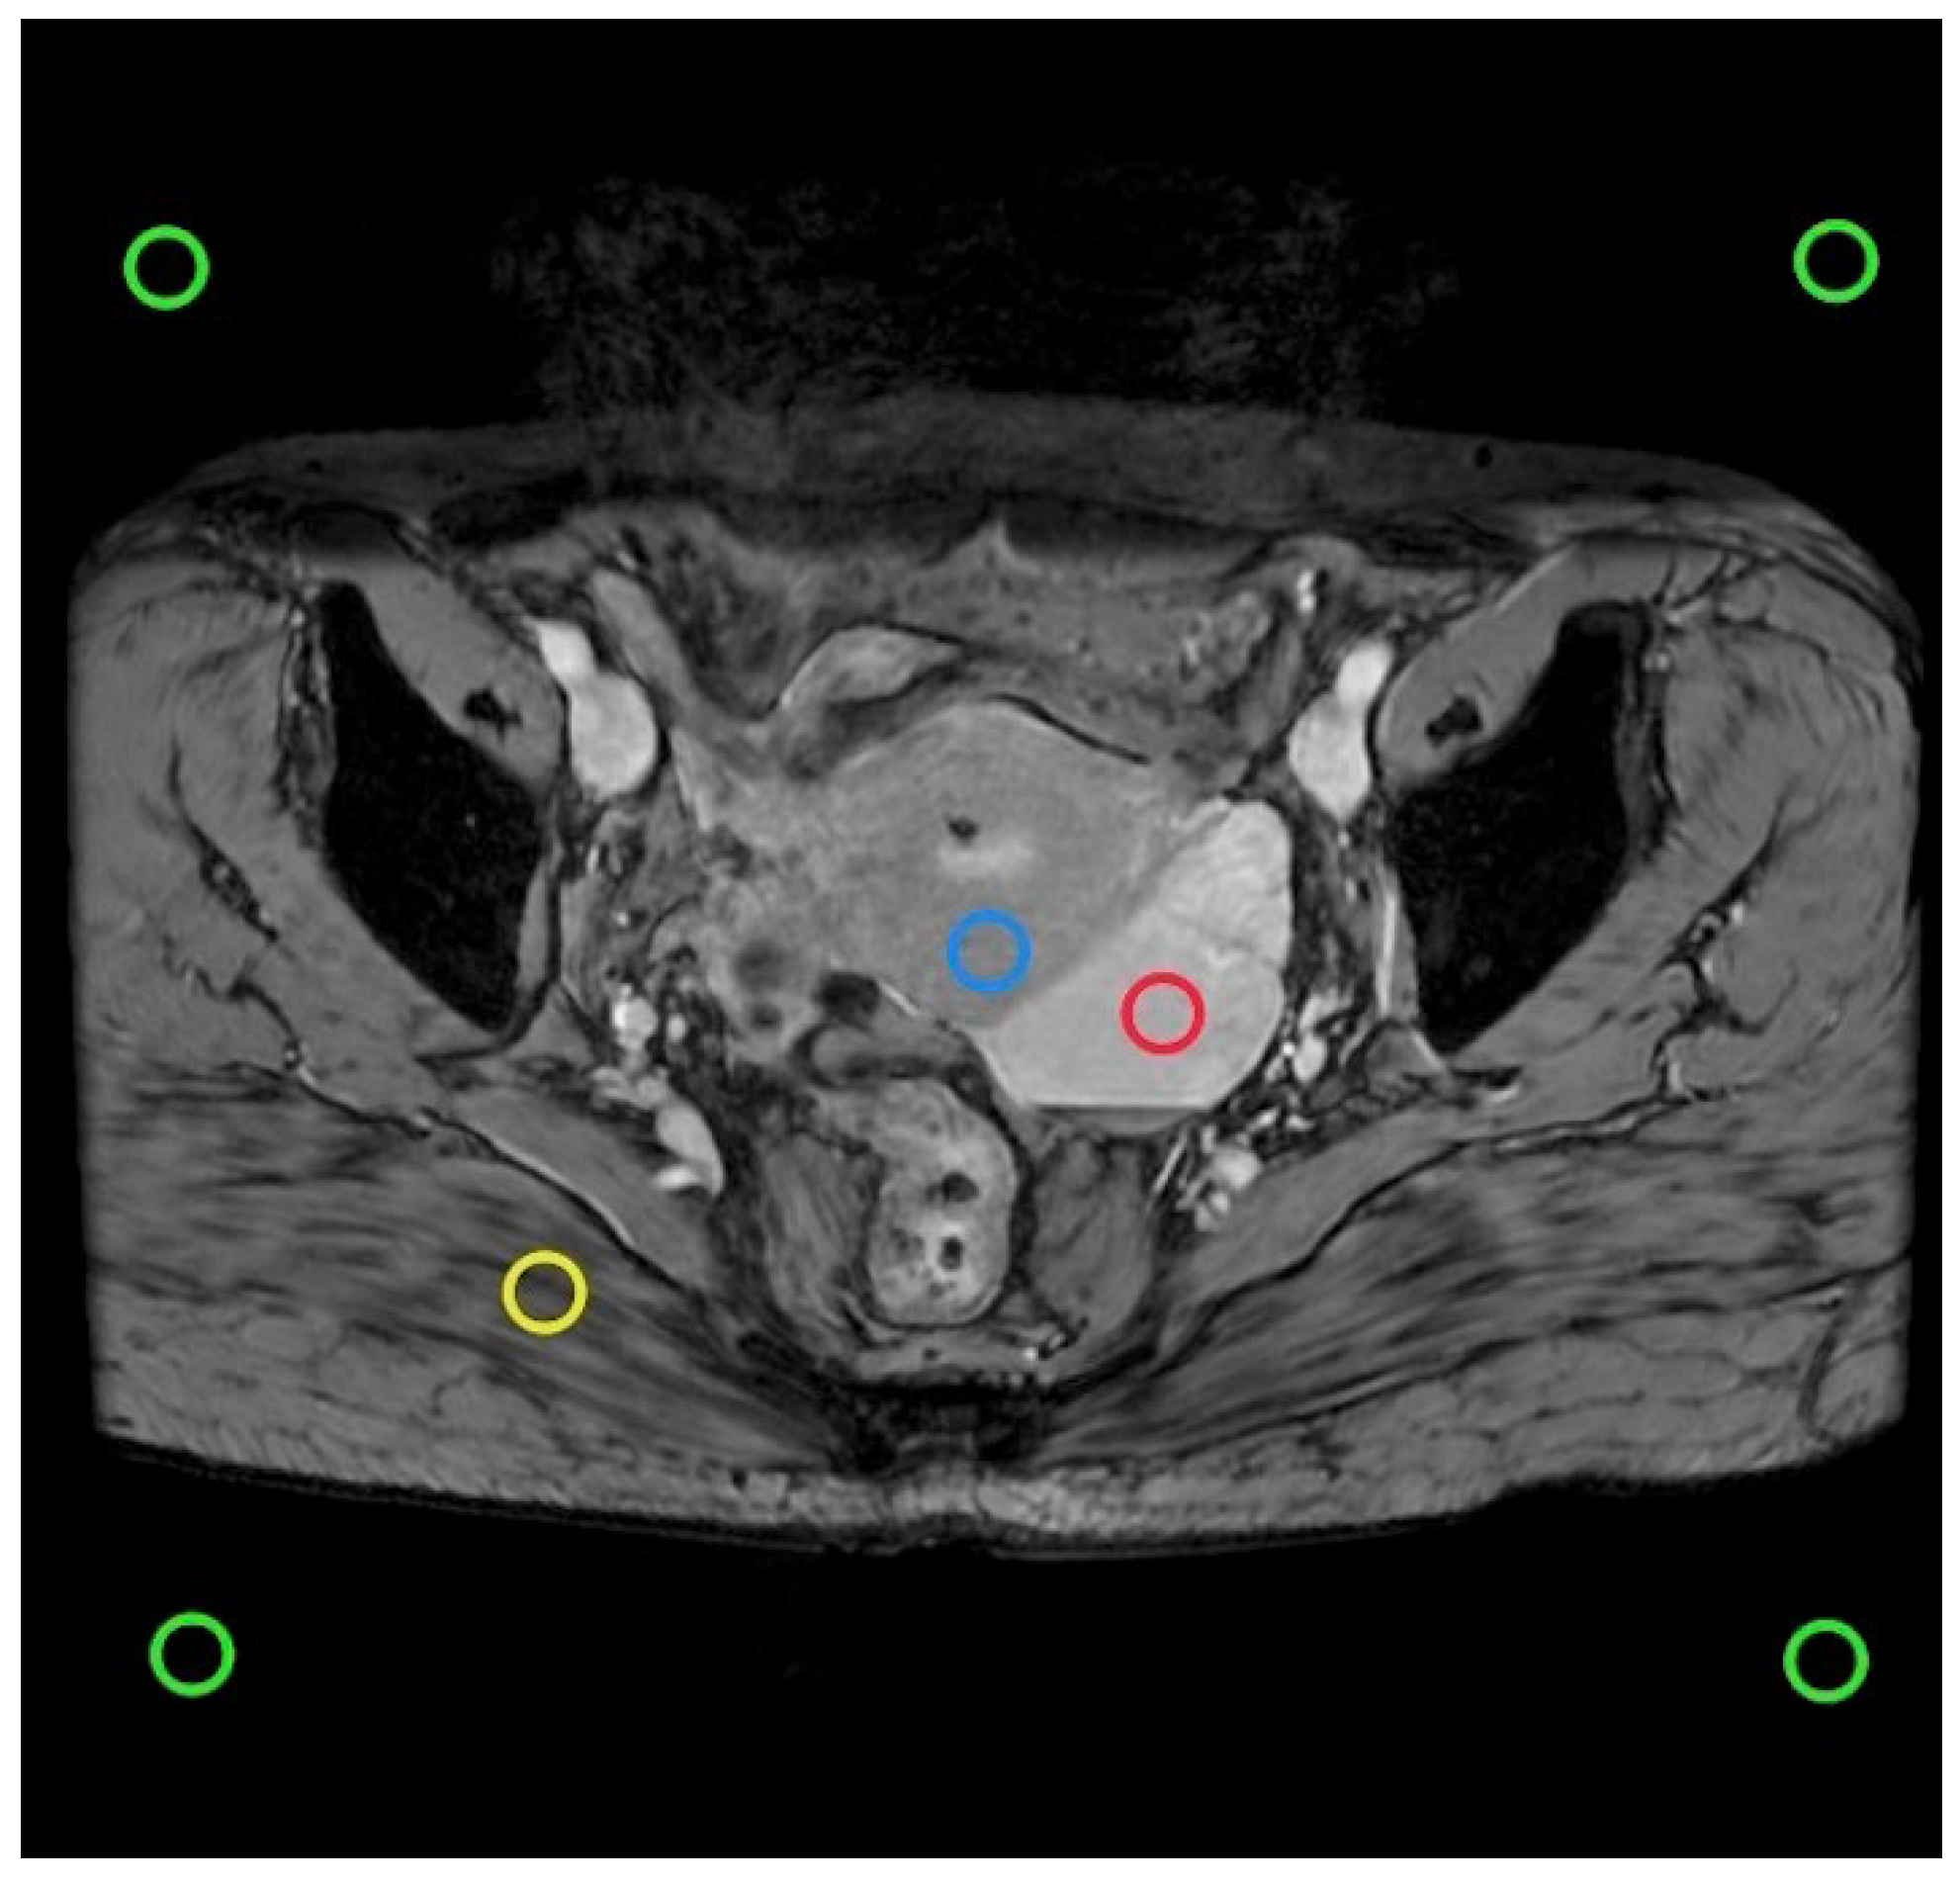

Figure 2. In the SWI intermediate layer, ROI (green) examples are plotted to estimate noise. Lesions are depicted in red, the uterus in blue, and the gluteus maximus in yellow. The pixel count within the ROI remains constant across different matrix sizes.

For each patient, the smallest lesion diameter of 0.5 ∼ 1.5 cm2 was selected as the ROI on the intermediate layer image slices containing lesions to avoid partial volume effects and examined by a radiologist with more than 1 year of FP-SWI experience (Figure 2).The ROI was plotted using the GE post-processing workstation AW4.7 and the morphological sequence was used as a reference. A minimum lesion diameter of 0.5 to 1.5cm2 was selected as the ROI to avoid partial volume effects.